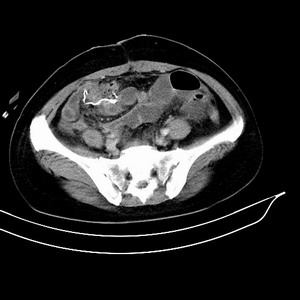

女 42岁 子宫肌瘤于外院术后两天,感腹胀。x线提示肠梗阻。

子宫肌瘤于外院术后两天,出现肠扭转梗阻,很明显。但右下腹部出现的线状高密度,是什么呢?有什么手术会有这样的物品呢?不会把电刀的导线遗留在腹腔吧!?

结果:术后纱布遗留,术后麻痹性肠梗阻肠梗阻

上面的图像是我们从手术室拿来的纱布做了个ct平扫,发现纱布里确实存在有一条致密影。后得知致密影是为防止手术时纱布遗留而设计。关腹时怀疑纱布遗留可做个床边透视或拍片可明确。